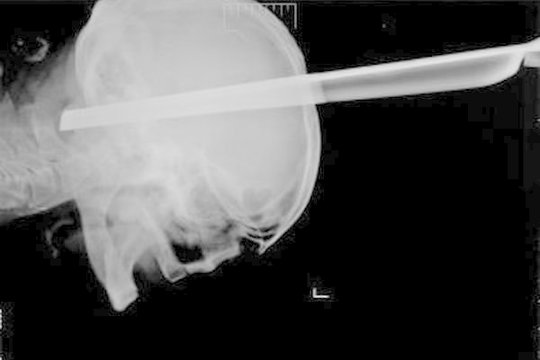

Rusijoje medikai pacientui iš galvos ištraukė taburetės koją

Pasaulis

2013-08-24